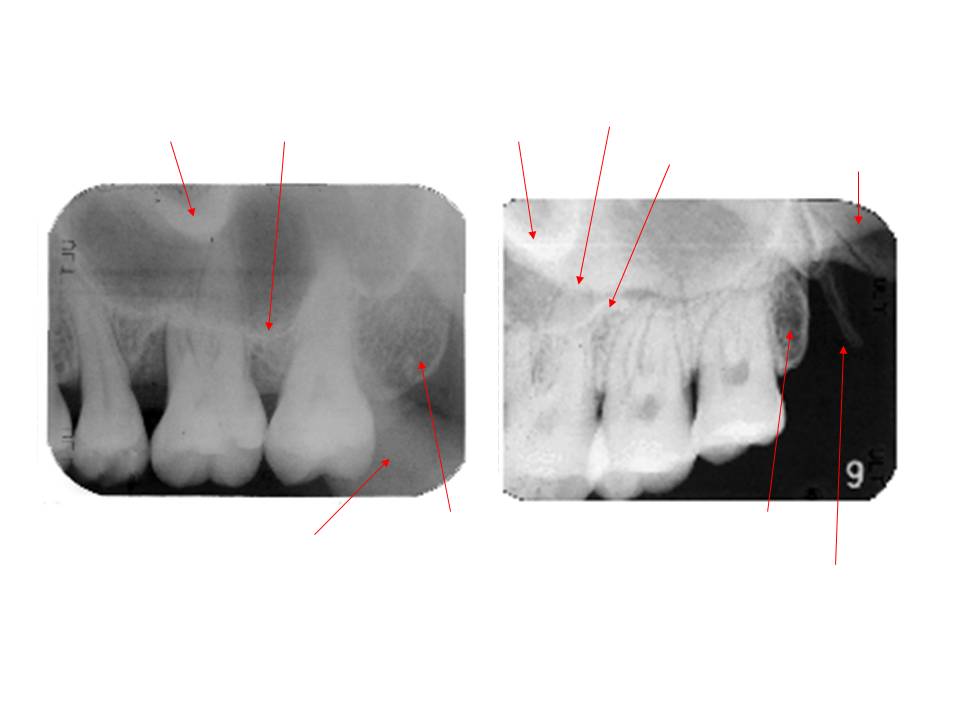

口内法(二等分法・咬合法)撮影の解剖